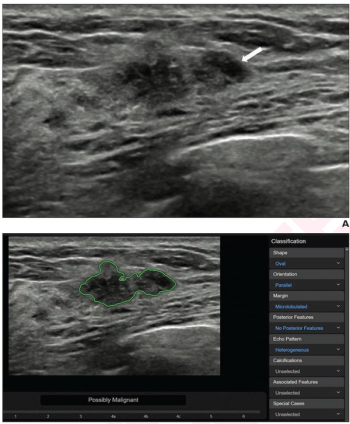

In a comparison of image-to-text large language models (LLMs), ChatGPT 4.0 offered a 95 percent sensitivity rate and an 83 percent AUC that were comparable to that of two senior radiologists and one junior radiologist interacting with LLM to differentiate between malignant and benign thyroid nodules on ultrasound.